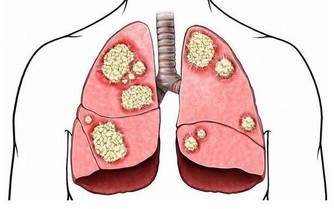

7、水使造血系統運轉正常,有助於預防某些類型癌症,特別是白血症和淋巴瘤。